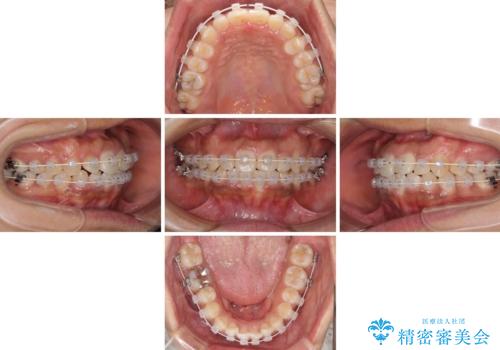

2年ほどインビザライン矯正を続けましたが、終了することができず、ワイヤーへ転換後は1年弱で終えることができました。